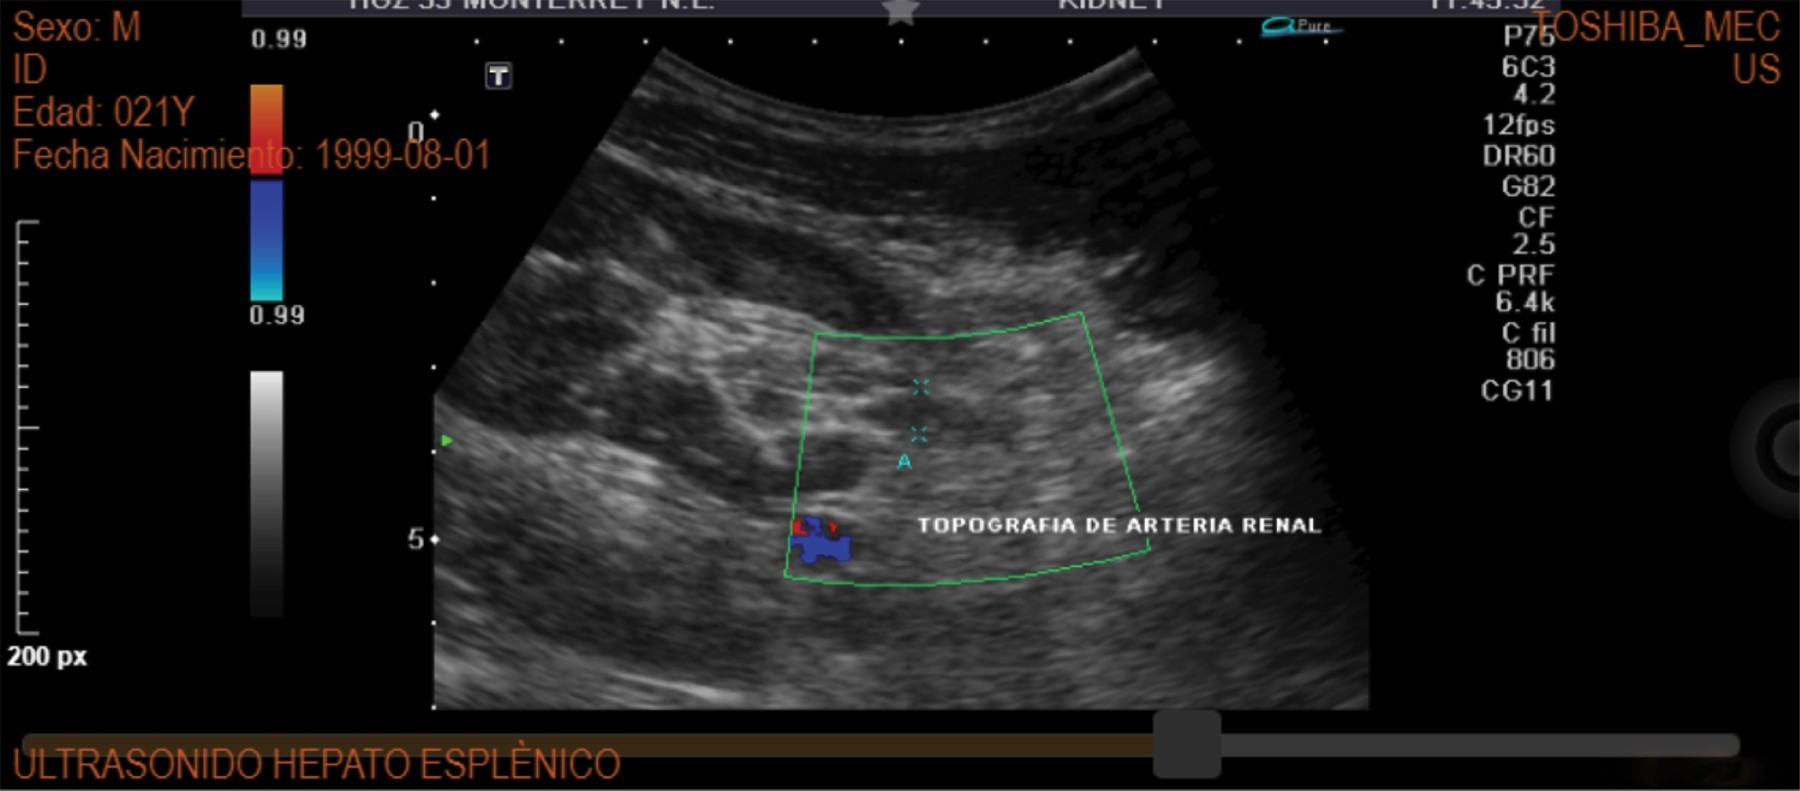

Figure 1